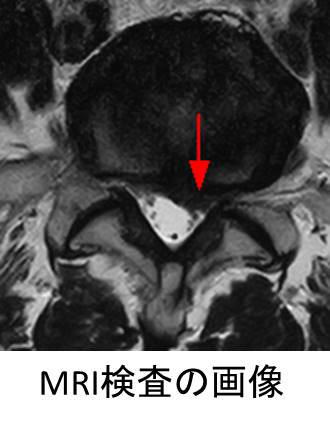

背骨は中央部に脊柱管という空洞があり、神経の通り道になっております。背骨と背骨の間は椎間板という軟骨があり、椎間板が破綻し、脊柱管に突出した状態を椎間板ヘルニアといいます。腰椎で椎間板ヘルニアが起きると、神経を圧迫することで下肢の痛みやしびれを起こしたり、運動の麻痺を起こすことがあります。